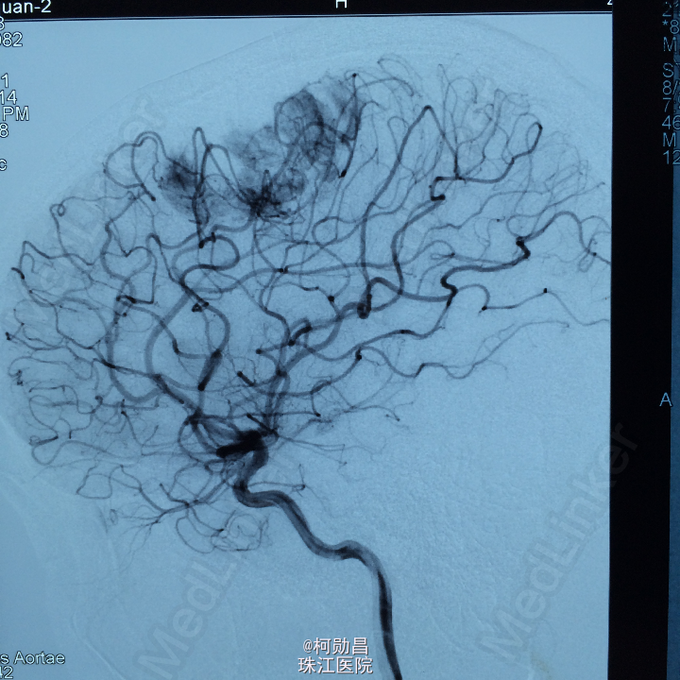

主诉:头痛伴右上肢麻木无力两个月,加重七天 病史:两个月前出现头痛,走路不稳,右上肢无力,不能持物,过去两个月曾有两次癫痫全面发作,发作时意识丧失,但无尿失禁及舌头咬伤。查头MRI示右侧顶叶占位,考虑脑膜瘤。

查体:巴氏征阳性,左侧肢体感觉减退,肌力正常,余无特殊阳性。 辅助检查:查头MRI示右侧顶叶占位,考虑脑膜瘤。

诊断:左侧顶叶占位 处理:行DSA检查,提示肿瘤染色,予PVA颗粒行血管内栓塞治疗。

术后再予开颅手术治疗,书中见供血动脉闭塞,出血量少。